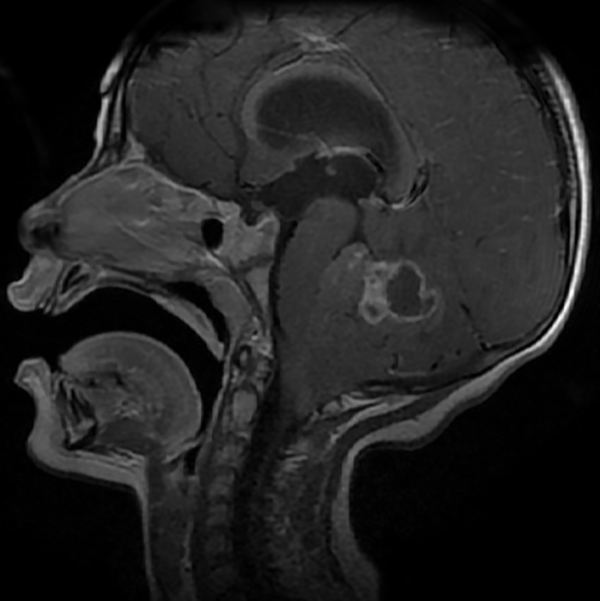

En resonancia magnética (RM) de cerebro se observa tumoración heterogénea sólida o sólido-quística con áreas de hemorragia, quistes y calcificaciones, que capta contraste en forma variable. (Fig. 1, 2, 3, 4). El patrón en espectroscopía se caracteriza por presentar pico de Colina (Cho) y descenso de N-Acetilaspartato (NAA).

Fig 1: RM corte axial, secuencia T1 con contraste. Se observa neoformación medial, solido-quística, heterogénea de bordes irregulares en la topografía del VI ventrículo que ocupa la totalidad del mismo, que realza en forma heterogénea tras la administración del contraste.